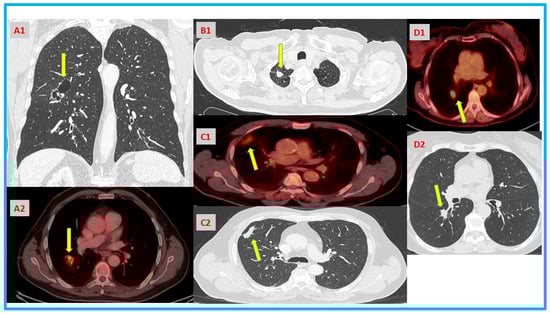

| Case | What Is the Problem | Performed Procedures | How the BSP Could Change Management |

|---|---|---|---|

| A | Cavitation with solid component that is not amenable for biopsy would need large resection. Elderly high-risk patient with a limited pulmonary reserve. | Bronchoalveolar lavage. | Validated positive result would help with shared decision making and avoid delay prior to surgery. |

| B | >3 cm lung mass in high-risk patient, not amenable for biopsy. | Patient request to postpone surgery for additional imaging. Later agreed for SBRT. | Validated positive result might help with shared decision making and avoid delay for definitive treatment. |

| C | Persistent consolidation in high-risk patient with negative biopsy. | Needle biopsy, follow-up repeated scans at 3,6 months. Delayed surgery finally. | Validated positive result would prompt earlier surgical intervention. Might avoid stage migration and adjuvant chemotherapy. |

| D | Borderline pulmonary function tests for lobectomy in high-risk patient for both lobectomy and SBRT. | EBUS, navigation bronchoscopy. Offered surgical resection. | Validated positive result would prompt earlier surgical resection. Would help in discussing the risks vs. benefits of surgery vs. SBRT with the patient. |

| E | Enlarging pulmonary nodule in previous hematologic cancer patient with additional tiny nodules. | Needle biopsy ×2. | Validated positive result would avoid second biopsy and prompt earlier surgical resection for definitive treatment. |